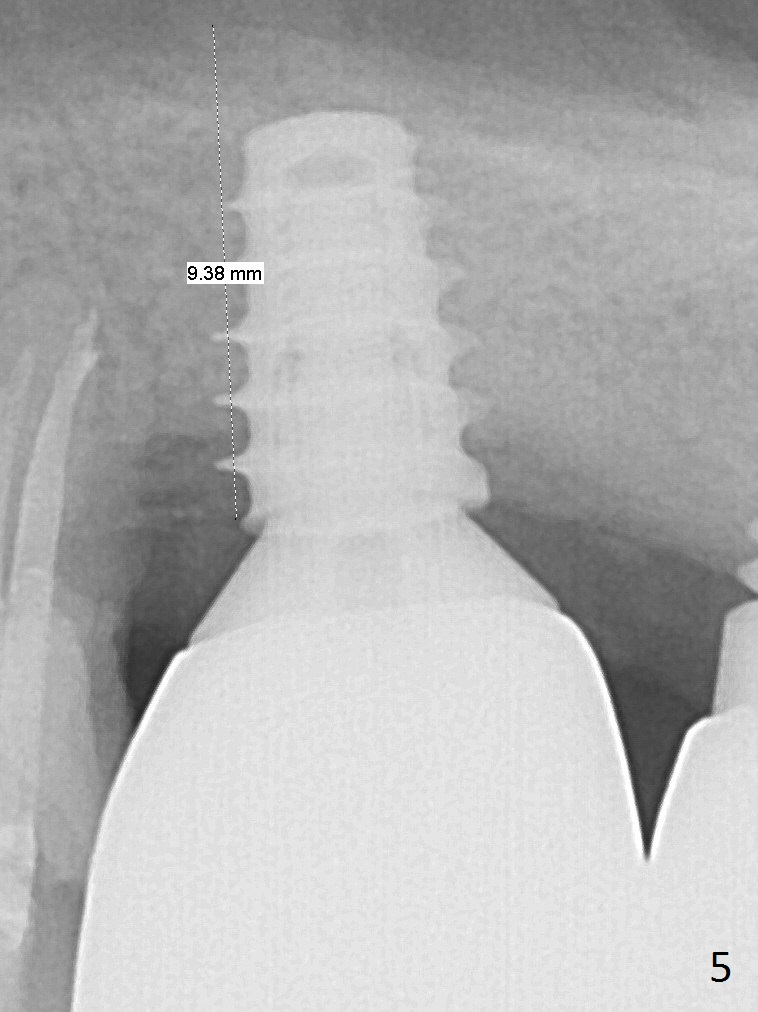

Four months post bone graft, the bone height at #14 is ~ 5 mm (Fig.1). After osteotomy for 4 mm with 4.3 mm Magic Drill (hard bone), Magic Sinus Lifter is used for sinus lift for ~ 8 mm without sinus membrane perforation. Perforation occurs with pulsating hemorrhage after sinus lift with allograft (.5-1 mm, mixed with Metronidazole). Collagen plug is used to repair the perforation before placing a short (5x7 mm) IBS implant with ~ 25 Ncm (Fig.2). After placing a 6.5x5.7(3) mm abutment, allograft is placed around the most coronal exposed implant thread (^). Acrylic is applied over the abutment for wound protection. There is mild nasal hemorrhage for 2 days postop. To prevent and treat sinus membrane perforation, PRF will be routine prepared preop for future cases. New bone forms apically and coronally 4.5 months postop (Fig.3,4 ^). A new temporary crown is fabricated so that it can undergo progressive loading for a few months before final impression. The definitive restoration is delivered 7.5 months postop (Fig.5). The bone density apical to the implant becomes apparently denser nearly 5 months post cementation (Fig.6). The bone density in the crest increases 2 years post cementation (Fig.7 *).